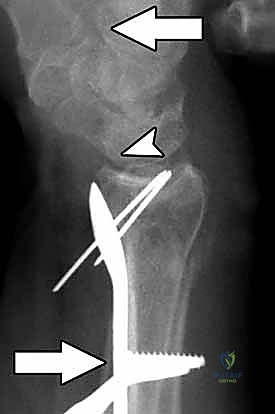

4. وضع الصفيحة والتثبيت المؤقت

يتم اختيار صفيحة تيتانيوم مصممة تشريحياً لتلائم انحناء الكعبرة. توضع الصفيحة على العظم وتُثبت مؤقتاً بأسلاك معدنية دقيقة (K-wires).

5. حفر العظم ووضع المسامير

يتم حفر ثقوب في العظم عبر فتحات الصفيحة، ثم تُقاس المسافات بدقة لإدخال مسامير القفل (Locking Screws) في الجزء البعيد (قرب المفصل) ومسامير قشرية في الجزء القريب (في ساق العظم).

6. الفحص النهائي والإغلاق

يتم إجراء فحص أخير بالأشعة للتأكد من المحاذاة المثالية للكسر وأطوال المسامير (لضمان عدم بروزها واحتكاكها بالأوتار الخلفية). بعد ذلك، يتم خياطة الأنسجة والجلد بخيوط تجميلية ووضع ضمادة معقمة.